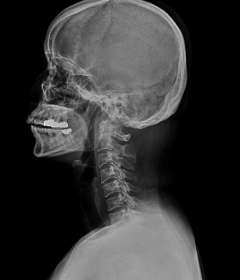

정상적인 목뼈는 C자 형태의 굴곡을 지니고 있습니다. 이를 "전만"이라고 합니다.

그러나 잘못된 자세나 생활습관으로 인해 목뼈의 모양이 일자로 곧게 뻗은 경우는 '일자목 증후군'이라고 하며, 더 심한 경우는 반대 C자 형태 즉, 역 C자 형태의 목을 '거북목 증후군' 또는 '자라목 증후군'이라고 합니다. 이는 의학적으로 경추 후만증으로 일컫습니다.

일자목